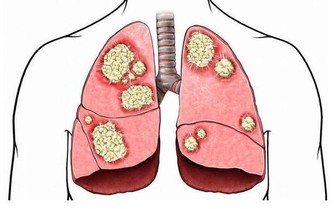

對於男性來說,男性患上腎臟疾病的機率要比女性高得多,尤其是尿毒症這種嚴重的腎臟疾病,就目前臨床數據顯示,男性患上尿毒症的機率是女性的好幾倍。所以,對於男性來說,可能要比女性更重視對自身腎臟的呵護,這樣或才能盡量避免尿毒症找上門來。

其實,男性若是想要知道自身的腎臟是否健康也很簡單,據醫生介紹,男性一般通過觀察自己一天的排尿情況,或就能看出腎臟的健康狀況,判斷自己是否被尿毒症這種腎臟疾病盯住了。

據了解,若是男性一天中的排尿次數接近“這個數”,那說明男性的腎臟還算健康,尿毒症還離得很遠,值得恭喜!但若是男性出現了這2種異常症狀時,那就需要提高警惕了,這些或都是尿毒症找上門的表現,是臨床上尿毒症的典型特徵。